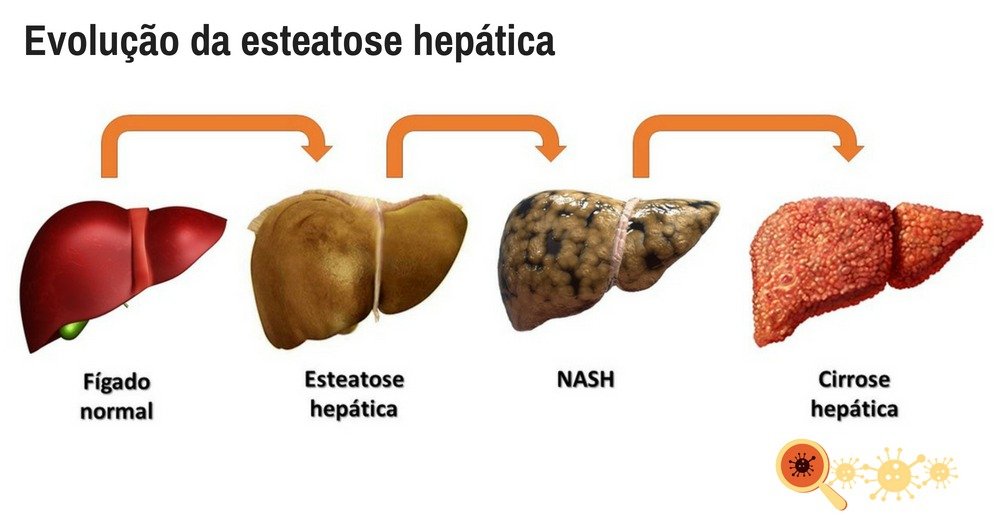

Médico afirma: quanto mais demorar para tratar, maior a chance de ter câncer no fígado

O que mais preocupa os médicos é o fato de que a maioria das pessoas que têm gordura no fígado, não sabem que tem isso.

De acordo com as autoridades médicas, quanto mais se demora a iniciar o tratamento, mais aumenta o risco de a Gordura no Fígado evoluir para problemas mais graves, como derrame, AVC, doenças cardíacas, diabetes, cirrose e até mesmo o câncer.